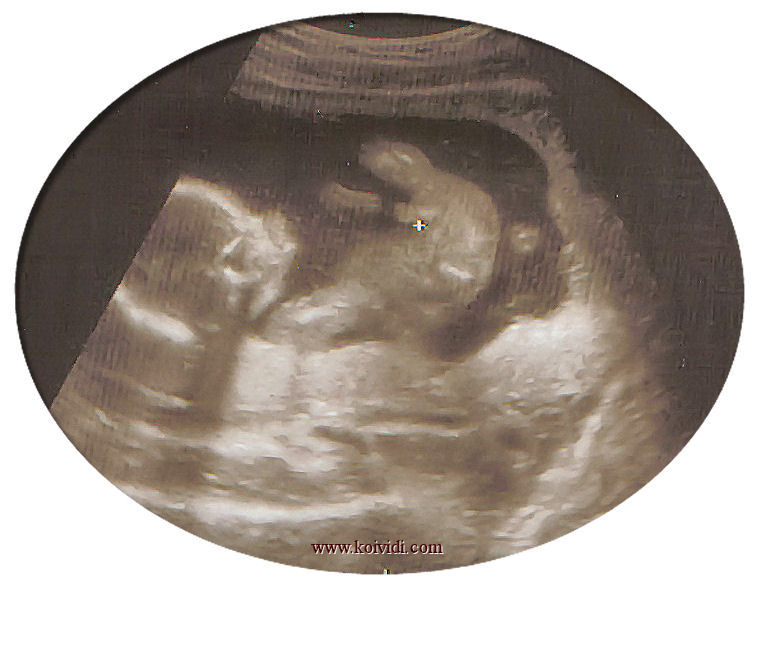

La première échographie est la preuve indéniable que vous êtes l’hôte d’un petit être qui va grandir et vous rendre heureuse au fil des mois.

On entendait son petit cœur qui battait la chamade, on distinguait déjà ses membres. Le lien se créait, cet enfant était le mien. Oui, déjà, le mien et le sien, lui qui se sentait déjà fier de celui qui sera un peu de lui et de moi.

Tout allait bien, son cœur, ses membres et on savait même le sexe du bébé. Un garçon, un petit garçon, pour moi et l’homme de ma vie: C’est un cadeau des Dieux, c’est sûr.